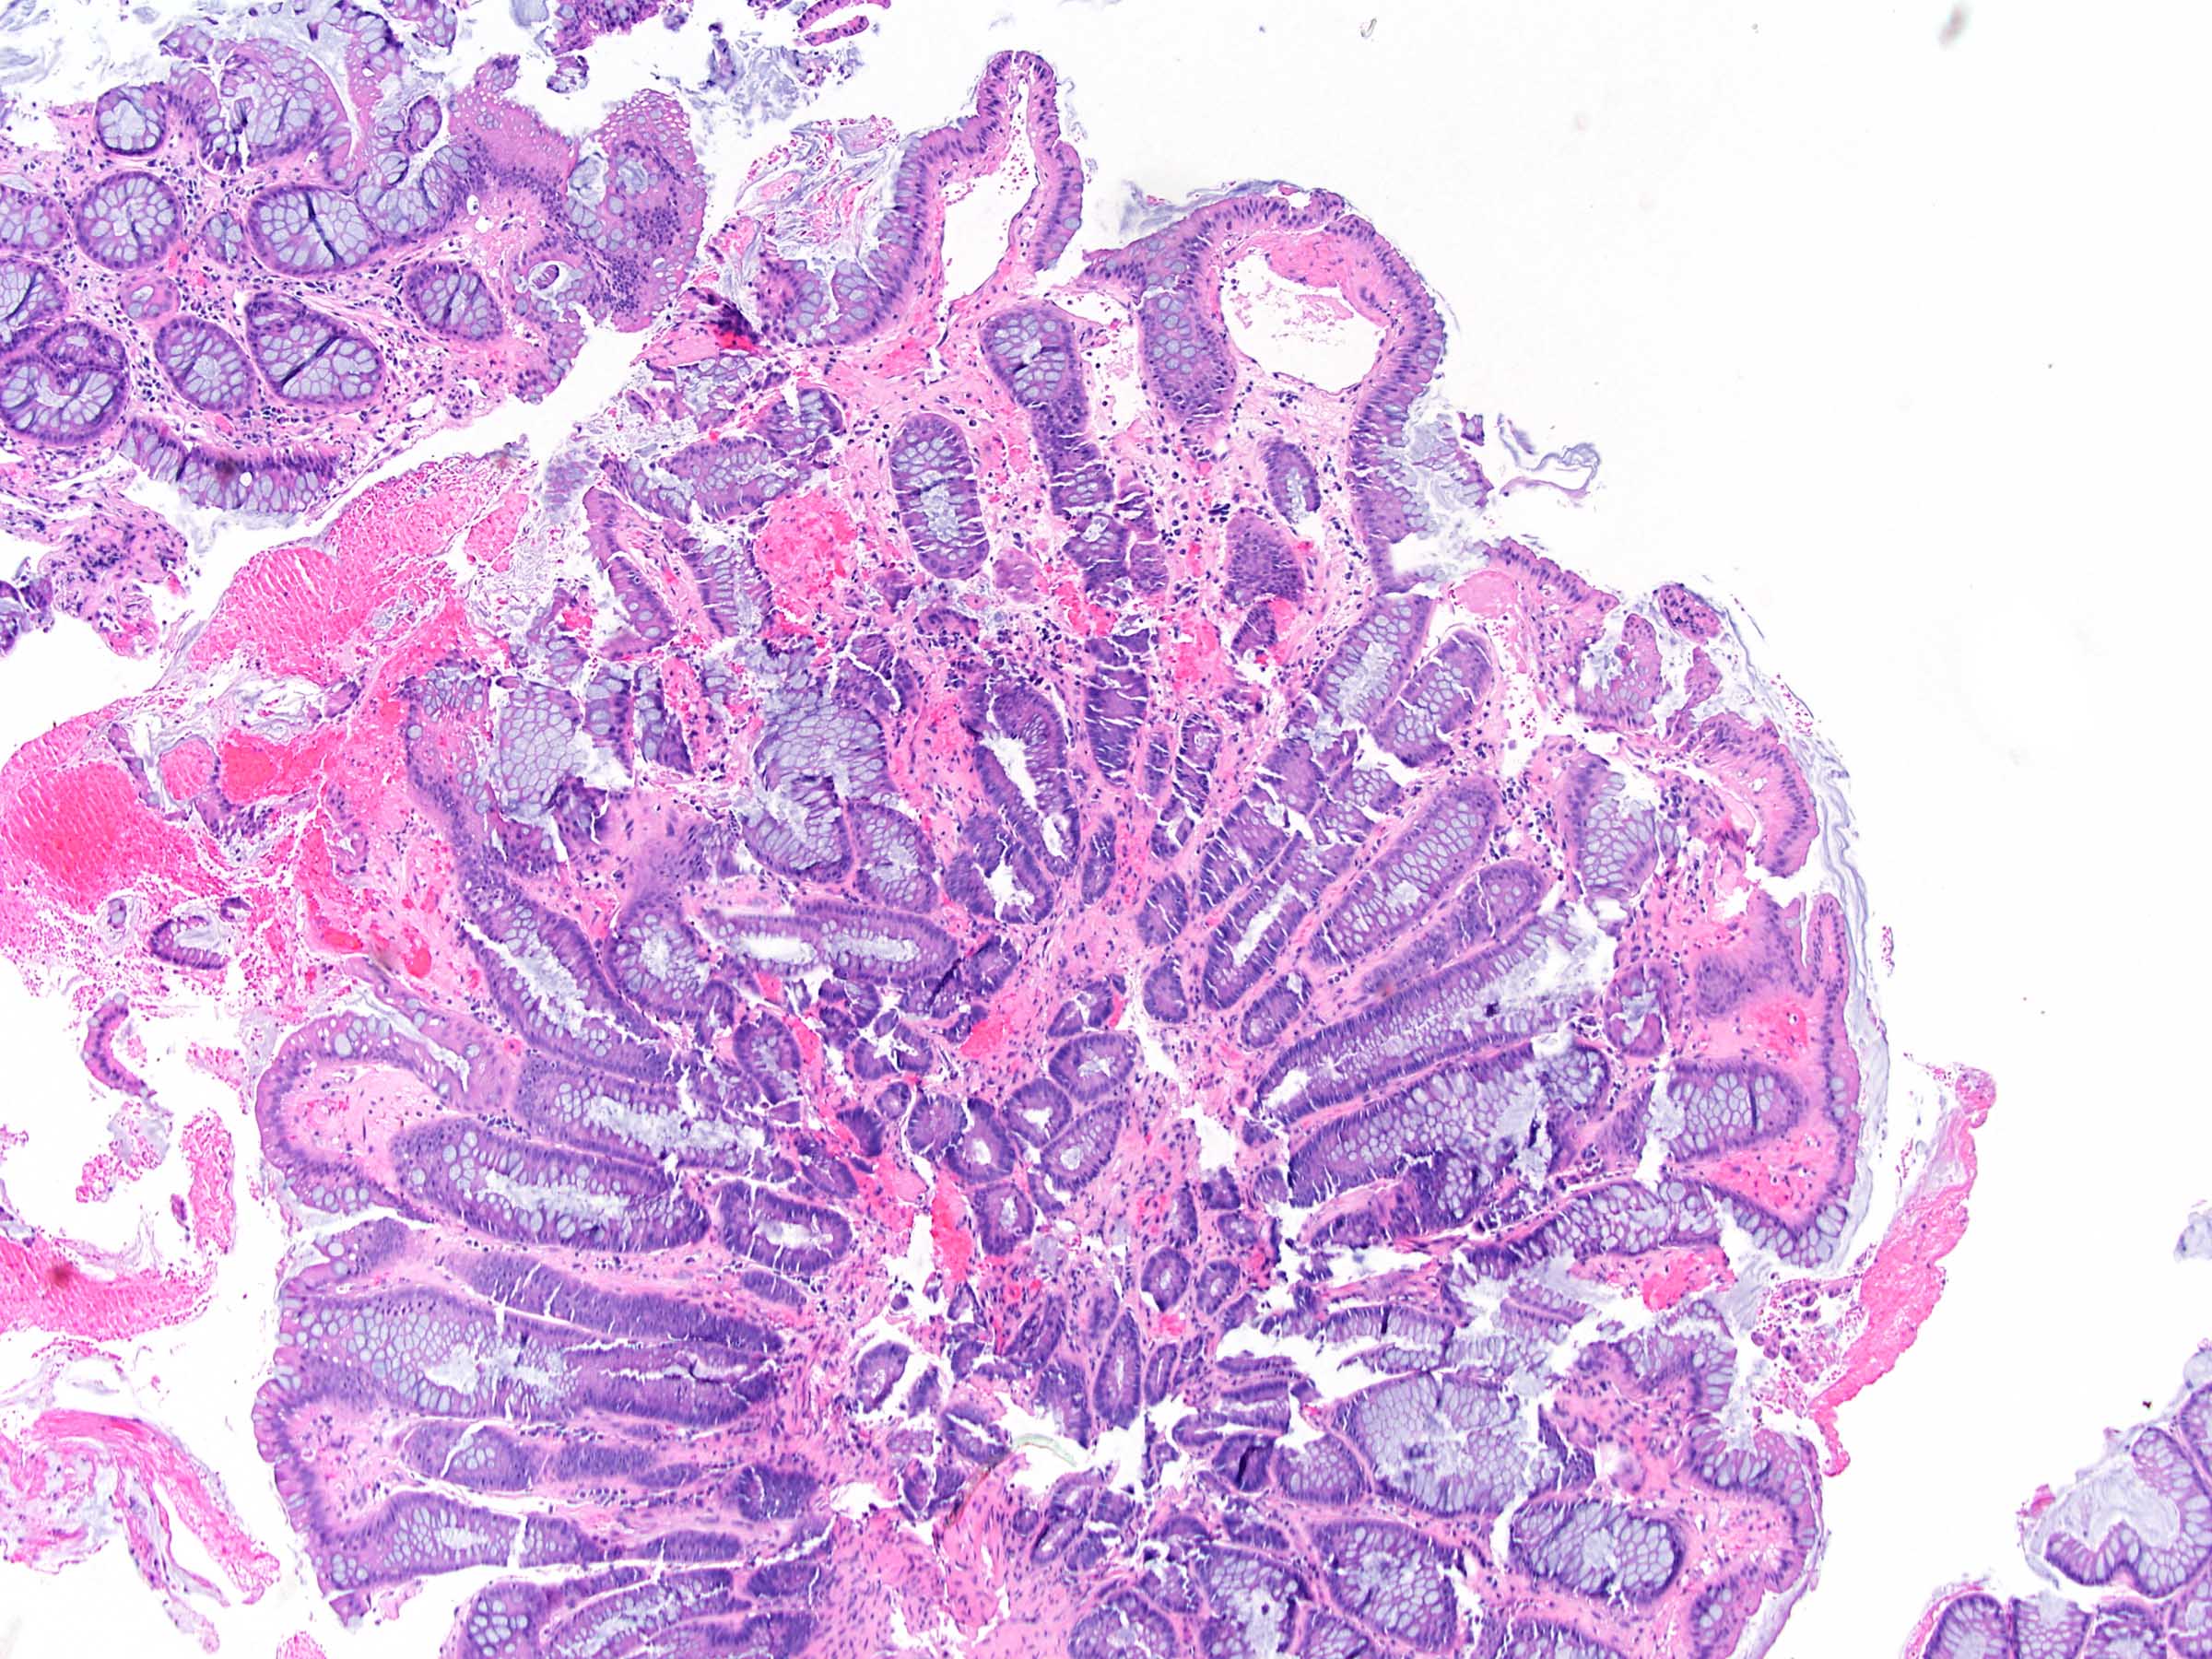

Microscopic (histologic) images

- Chronic radiation colitis (> 6 months after radiation treatment):

- Epithelium:

- Paneth cell metaplasia

- Ulceration

- Mild epithelial atypia

- Crypts:

- Architectural changes and atrophy

- Lamina propria:

- Fibrosis

- Mild chronic inflammation

- Atypical fibroblasts / stromal cells with enlarged hyperchromatic nuclei

E. Radiation colitis, chronic. Chronic radiation colitis is expected at > 6 months postradiation therapy. Sections show ulcerations, mild epithelial atypia, architectural changes and atrophy. The lamina propria contains fibrosis, mild chronic inflammation and fibroblast atypia (enlarged hyperchromatic nuclei). The vasculature within submucosal and deeper layers contains hyalinization of vessel wall and intimal thickening. Vascular ectasia, narrowing and thrombosis can also be present. Collagenous colitis (answer A) typically presents with history of watery diarrhea and a > 10 μM subepithelial collagen table (collagenous band). Infection (bacterial) (answer B) will present with an acute clinical history (example: diarrhea and vomiting) after an inciting event (example: food consumption, travel). Acute colitis and granulomas can sometimes be seen. Viral infections (example: cytomegalovirus, Epstein-Barr virus) can occur in immunocompromised patients (example: HIV or transplant) and will contain atypical cells with nuclear changes. Mucosal prolapse (answer C) can present endoscopically as a polyp and contains ingrowth of thick muscle bundles that can mechanically squeeze ensnared epithelium. This is accompanied by variable inflammation, ulceration and reaction epithelial change. Acute radiation colitis (answer D) is expected at < 6 months postradiation therapy. The inflammation is typically eosinophilic (characteristic) with eosinophilic cryptitis, crypt abscesses and lamina propria eosinophilia. Sections demonstrate reduced mitotic activity, apoptosis, reduced goblet cell mucin, goblet cell swelling, degenerative changes and atypia (nuclear enlargement and malorientation).